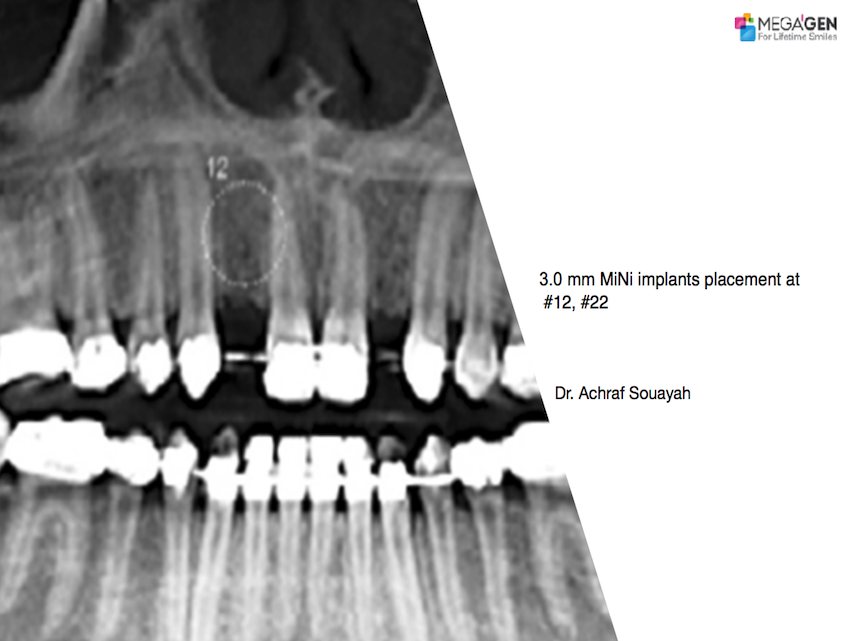

Dr. Hyung Jun Kim,Edentulous,Maxillary Anterior,Maxillary Posterior,Mandibular Anterior,Mandibular Posterior,#12,#22,#32,#45,#14,#24,#36,#46,#15,#25,#37,#47,#17,#27,#41,Immediate Placement,AnyRidge,Full-mouth implants,Full mouth rehabilitation,Octa abutment,Long-term clinical case,Biological stability